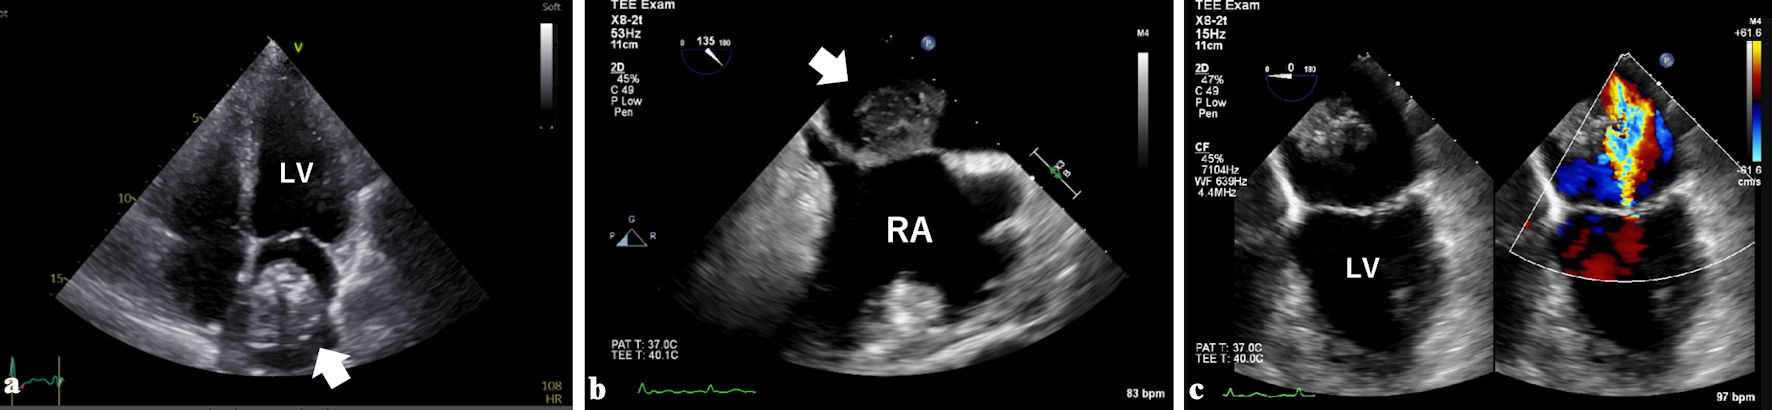

Subsequently, cardiac magnetic resonance (CMR) imaging was performed for histological discrimination of the tumor. The interior of the mass was hypointense on T1-weighted (T1w) and T2-weighted (T2w) imaging, and the exterior was hyperintense on T2w imaging (Fig. 3a, b). No change was observed on fat suppression imaging. Late gadolinium enhancement (LGE) imaging showed heterogeneous enhancement (Fig. 3c). These findings were consistent with myxoma.

Figure 3. Cardiac magnetic resonance imaging showed that the interior of the mass was hypointense on T1-weighted (a) and T2-weighted imaging (b), and the exterior was hyperintense on T2-weighted imaging. Heterogeneous enhancement was observed on late gadolinium enhancement imaging (c).